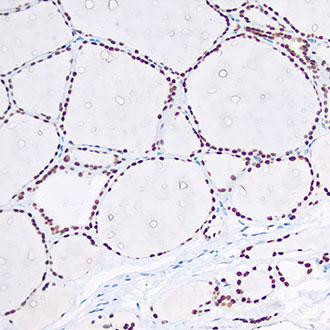

PMS2

PMS2 -